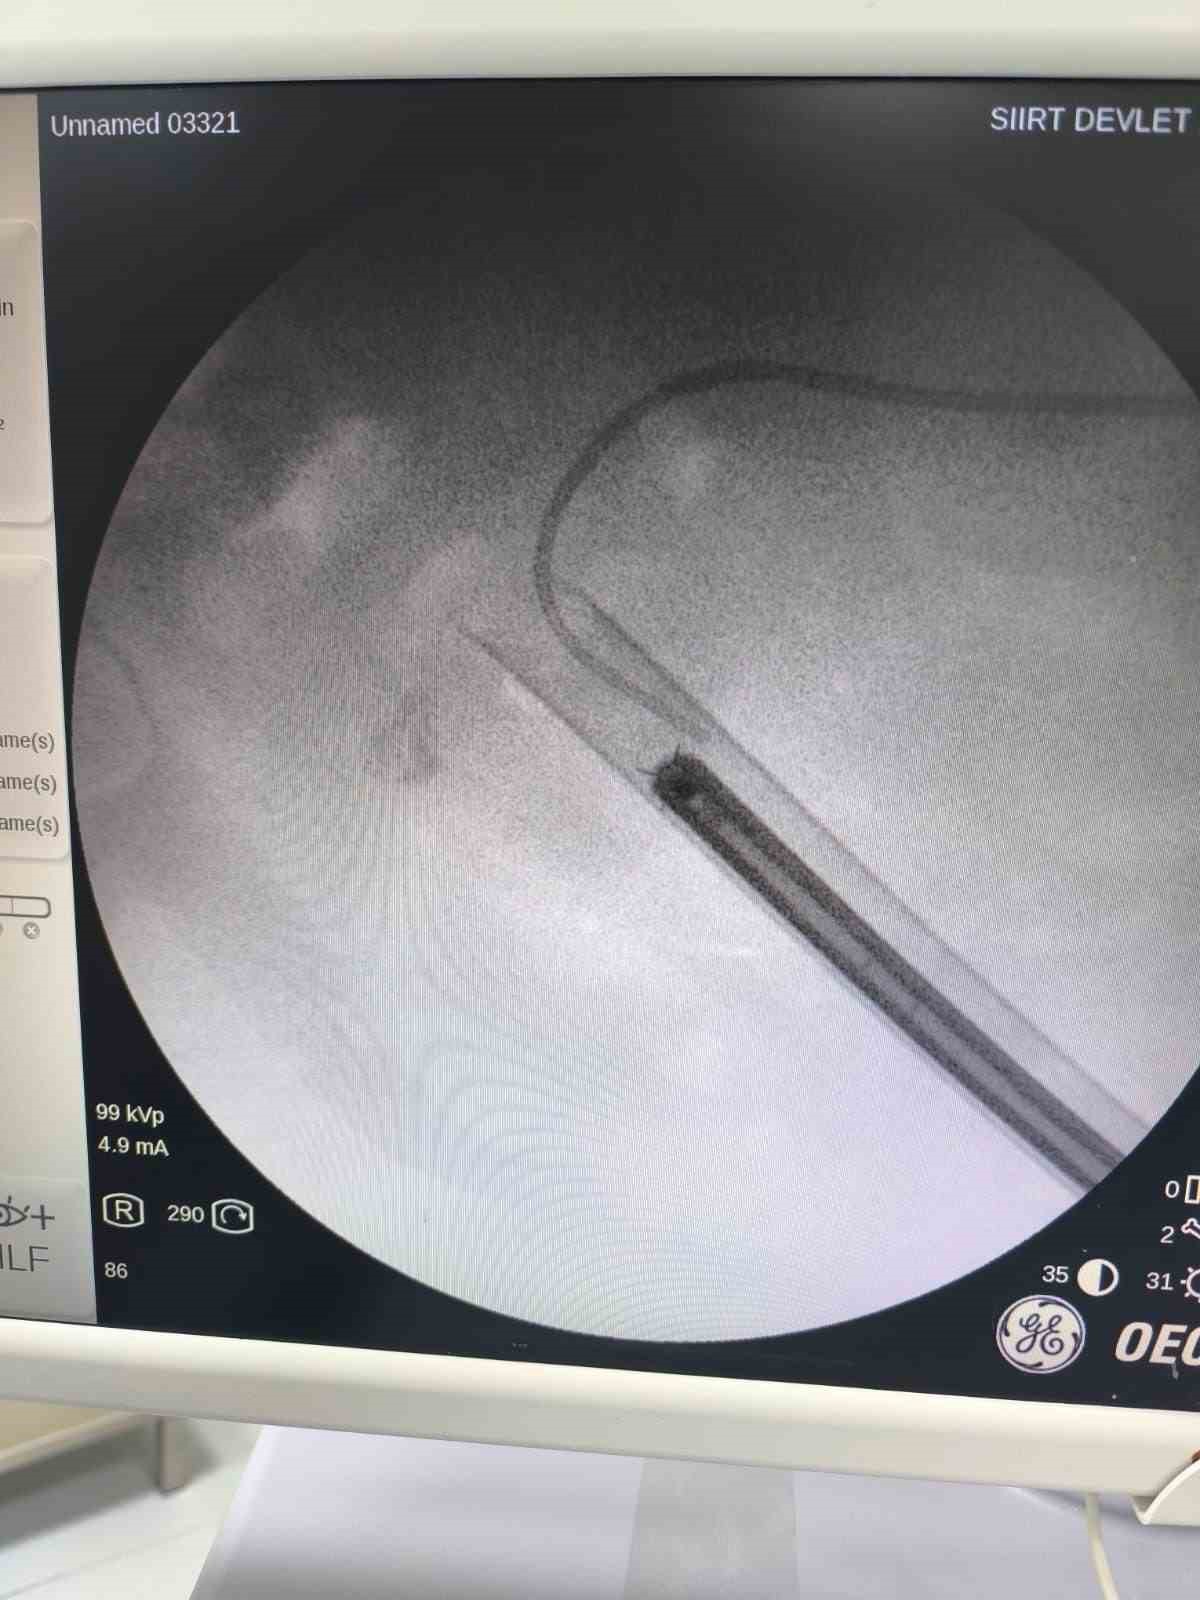

Siirt’te 34 yaşındaki Fatih Aslan, ateş, üşüme ve idrar yaparken yanma şikayetleriyle hastaneye başvurdu. Yapılan muayene ve testlerin ardından piyelonefrit (böbrek iltihabı) tanısı konuldu ve enfeksiyon tedavisi tamamlandı. Üroloji uzmanı doktor Miraç Ataman, gerçekleştirilen operasyon, hem tıbbi açıdan hem de toplumsal sağlık açısından önemli bir başarı olduğunu söyledi. Ataman, “34 yaşındaki erkek hastamız, ateş, üşüme ve idrar yaparken yanma şikayetleri ile acil servise başvurdu. Yapılan değerlendirme sonucunda piyelonefrit (böbrek iltihabı) tanısı konuldu ve yatış yapılarak enfeksiyon tedavisi başarıyla tamamlandı. Tanı sürecinde yapılan Bilgisayarlı Tomografi (BT) görüntülemesinde böbreğin tamamını kaplayan, sert yapıda(950-1450 HU), literatürde staghorn olarak adlandırılan ve halk arasında ‘ geyik boynuzu taşı ’ diye bilinen büyük taş saptandı. Staghorn taşlar böbreğin tüm boşluklarını doldurup, tekrarlayan enfeksiyonlara ve uzun vadede böbrek fonksiyon kaybına yol açabildiğinden tedavisi hayati önem taşımaktadır. Biz de bu vakamızda, Perkütan Nefrolitotomi (PCNL) yöntemiyle böbreğe küçük bir cilt kesisi üzerinden girerek endoskopik cihazlarla taşları parçalayıp çıkardık. PCNL, özellikle çapı 2 cm’den büyük ve kompleks taşlarda altın standart kabul edilmektedir. Normalde staghorn taşların temizlenmesi uzun süren ve çoğu zaman birden fazla seans gerektiren zorlu bir süreçtir. Modern altyapısı sayesinde, ciltten tek giriş yolu açılarak yaklaşık 1,5 saatlik bir seansta böbreğin tüm taş yükü başarıyla temizlendi” dedi.